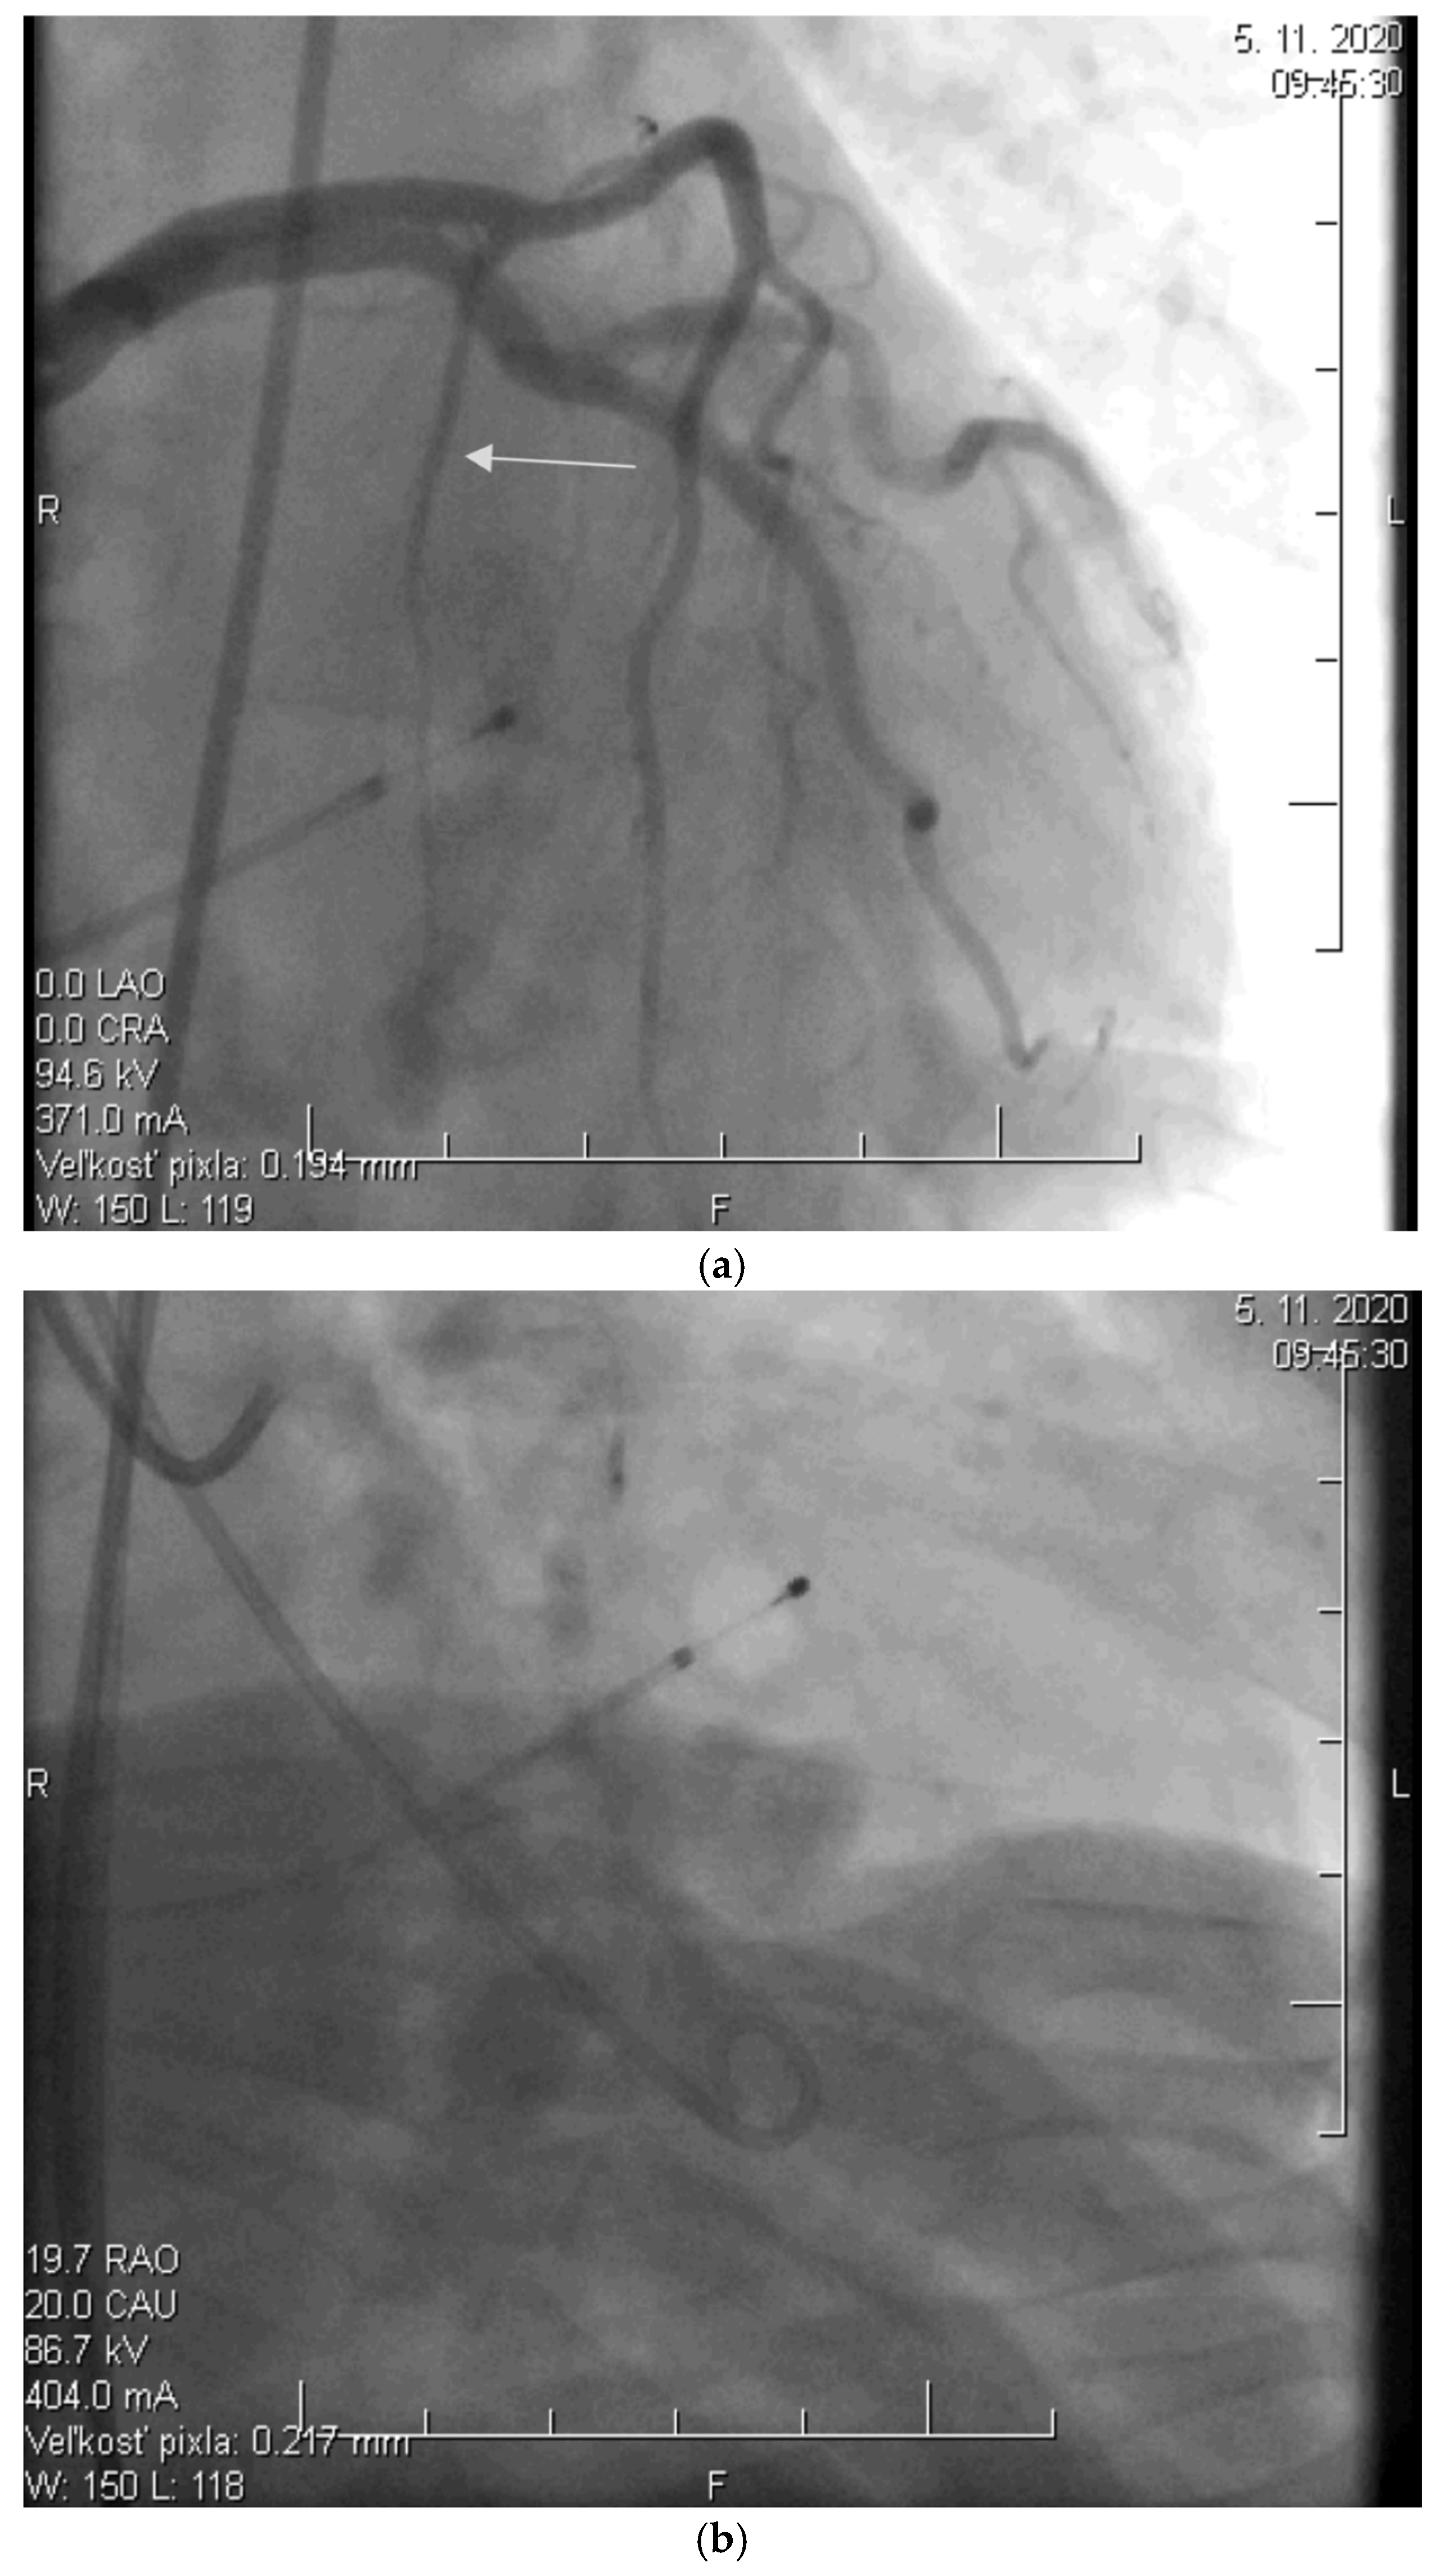

Before the procedure, a temporary pacemaker was inserted into the RV via a venous approach to prevent potential periprocedural conduction disorders. After the pacemaker was placed, selective injection of the left coronary artery was performed via a transfemoral approach to assess the anatomy of its branches (Figure 2a). Using a pigtail catheter introduced into the LV, the pressure gradient between the LV apex and the aorta was measured at rest and after provocation with a ventricular extrasystole, Valsalva maneuver, or, less frequently, nitrate administration.

Subsequently, a specialized over-the-wire balloon catheter was inserted into the septal branch supplying the area contributing to the LVOT narrowing (most commonly the basal interventricular septum. The balloon catheter was inflated to occlude the lumen of this vessel, followed by the injection of an echocontrast agent and echocardiographic assessment of the perfusion area and localization of the selected septal branch (echo-guided approach). After identifying the appropriate septal branch, 96% alcohol in a volume of 2 mL was administered uniformly to all patients according to internal protocol (Figure 2b).

Ten minutes after the alcohol application, the balloon was deflated, and the residual pressure gradient between the LV apex and the aorta was measured at rest and after the aforementioned provocative maneuvers. To conclude the procedure, a selective injection of the LCA was performed to confirm the ablation of the septal branch and exclude potential alcohol leakage into other parts of the coronary circulation, which could cause the no-reflow phenomenon (Figure 2c).

Figure 2. (a) Angiographic image of the left coronary artery showing a septal branch (arrow) (photo and copyright: T.P.). (b) Administration of 96% alcohol into the septal branch using an over-the-wire (OTW) balloon catheter (photo and copyright: T.P.). (c) Final effect of ASA with Closure of the Septal Branch (photo and copyright: T.P.).